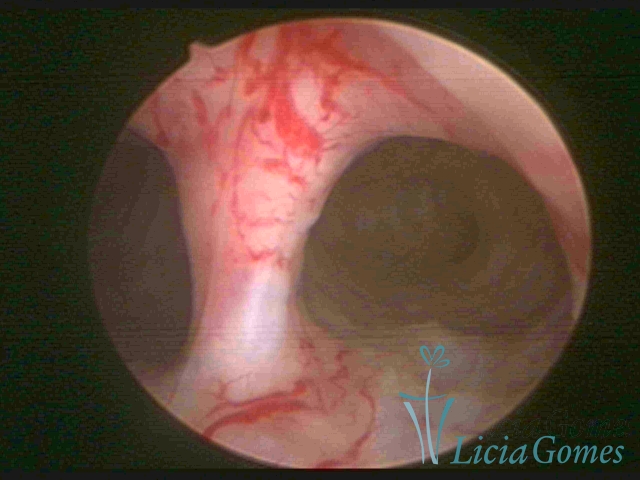

Septate uterus

It probably occurs by the lack of resorption on the middle line, in the merge of Müllerian ducts. The uterus is divided by a partial or total septum which is viewed as a crossbar, not covered by endometrium, which not bleeds when sectioned.

Complete septum when it occupies the whole extension of the cavity, dividing it into two hemicavities.

When this septum occupies only a part of the extension of the uterine cavity, it is considered as incomplete.